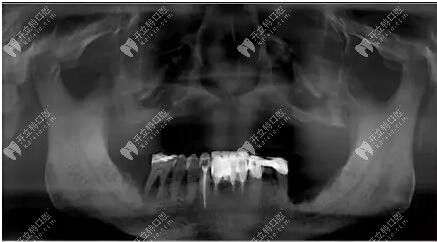

經(jīng)過拍片檢查上頜前牙區(qū)垂直骨較少,雙側(cè)上頜竇氣化明顯,患者選擇allon4和上頜結(jié)節(jié)種植,即刻修復(fù)。采用的是數(shù)字化導(dǎo)板種植,對于種植位置比較準(zhǔn)確。

拍片檢查上頜位置